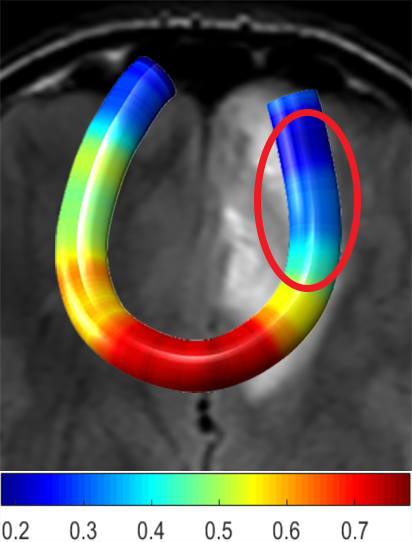

We performed pairwise comparison between two scans of a 32-year-old basketball player, diagnosed with mild occipital traumatic brain injury and frontal hemorrhage due to contrecoup impact, acquired one week and 6 months post-injury. The hemorrhagic lesion at the frontal right hemisphere of the player is no longer visible in the FLAIR image acquired 6 months after injury (Fig. 2a). Local differences between corresponding, longitudinal FA- and MD-FFDD profiles of the FMT (chosen due to its proximity to the lesion area) are shown in Fig. 2d. Figs. 2b-c present color-coded FMT to visually demonstrate these differences. Results show significant longitudinal variability at the right hemisphere part of the tract, corresponding to the lesion area, and relatively minor differences along the rest of the tract. These results should be considered as a proof of concept, validating the FFDD analysis results for the detection and localization of mTBI-related variabilities between fiber bundles.

| ONE WEEK | ![]() |

![]() |

FA-FFDD |

| 6 MONTHS | ![]() |

MD-FFDD |

| (a) FLAIR | (b) FA-FFDD | (c) MD-FFDD | (d) Local Differences |